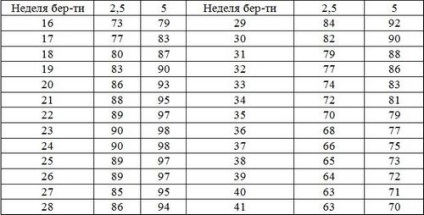

Külön figyelmet ellenőrzésében terhes nők mutatói érdemelnek a magzatvíz index 5-2,5 százalékos egy adott terhességi kor. Az alábbiakban feltüntetett számok.

Indikátorok magzatvíz indexe 2,5 és 5 százalék.